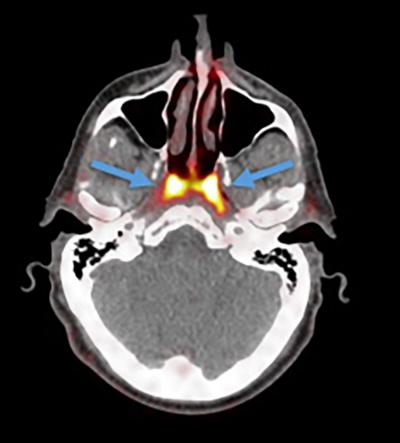

Researchers at the Netherlands Cancer Institute have identified a set of salivary glands deep in the upper part of the throat and have named them “tubarial salivary glands”.

The discovery may be important for cancer treatment. So far, this nasopharynx region — behind the nose — was not thought to host anything but microscopic, diffuse, salivary glands.

The newly discovered glands are about 1.5 inches (3.9 centimeters) in length on average and are located over a piece of cartilage called the torus tubarius, Livescience reported. According to the researchers, the glands probably lubricate and moisten the upper throat behind the nose and mouth.

The new organ was discovered while scientists were studying prostate cancer cells using PSMA PET-CT technology — a combination of CT scans and positron emission tomography (PET) — which is good in detecting salivary gland tissues. In this technique, a radioactive “tracer” is injected into the patient that binds to the protein PSMA, which is elevated in prostate cancer cells.